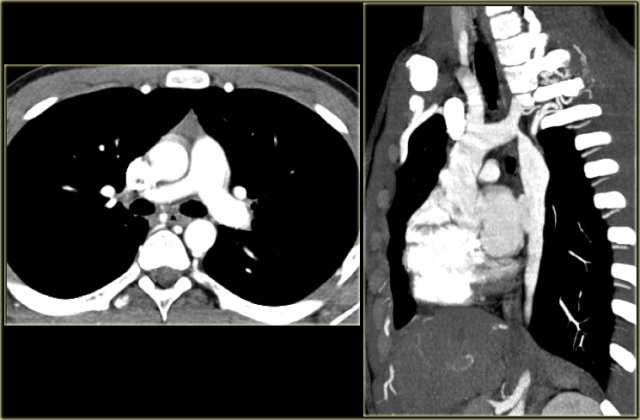

Pulmonary Sling Pulmonary Sling

Pulmonary Sling

On the left a 4 month old girl with abnormal echo, benign heart murmur and no respiratory or feeding difficulties.

The sagittal reconstruction shows an anomalous vessel on the posterior side of the trachea.

There is a little mass effect on the trachea.

In pulmonary sling the left PA originates from the right PA and courses between the esophagus and the trachea, where it compresses the right main bronchus.

Pulmonary sling is seen more frequent in children as it is more symptomatic than in adults, because the chest is smaller, but you can also encounter it in adults.

Pulmonary Sling with long segment stenosis of the trachea. (Courtesy J. Schoef) Pulmonary Sling with long segment stenosis of the trachea. (Courtesy J. Schoef)

On the left images of a child with wheezing and dyspnea.

The left PA comes off the right PA and runs between the esophagus (with nasogastric tube) and the trachea.

Some of these patients also have long segment stenosis in the trachea because of cartilagenous rings.